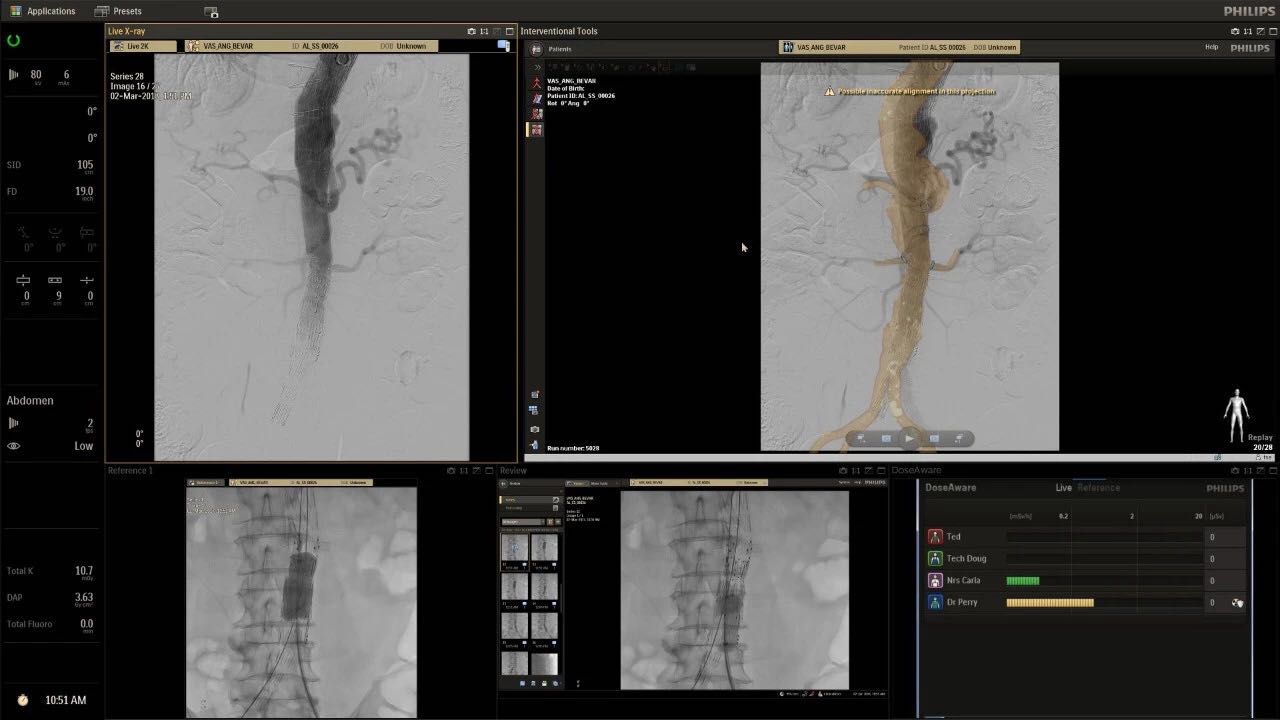

(FlexArm C型臂可以沿著工作臺的兩側(cè)提供偏心成像。這允許醫(yī)生在左臂或右臂上進(jìn)行徑向進(jìn)入病例,完全或部分伸展,而無需移動(dòng)患者或樞轉(zhuǎn)桌子。X射線束與手臂保持對齊,以促進(jìn)其整個(gè)長度的平滑導(dǎo)航,而無需進(jìn)行持續(xù)調(diào)整。)

飛利浦表示,采用FlexArm設(shè)計(jì)的Azurion 7 C20可提供卓越的靈活性和直觀的控制。該系統(tǒng)由智能運(yùn)動(dòng)引擎驅(qū)動(dòng),可在八個(gè)不同的軸上移動(dòng),所有這些軸均由其單個(gè)“Axsys”控制器控制。臨床醫(yī)生的模擬測試表明,該系統(tǒng)有可能顯著減少患者,工作人員和設(shè)備的重新定位,從而改善微創(chuàng)手術(shù)的可及性,包括通過患者手腕進(jìn)入身體的手術(shù)(橈動(dòng)脈入路),并降低患者的風(fēng)險(xiǎn)。無意中拔出電線和管子,以及節(jié)省大量時(shí)間。該系統(tǒng)非常適合混合手術(shù)室(OR),可滿足一個(gè)房間內(nèi)的多種專業(yè)需求,例如手術(shù)和血管內(nèi)手術(shù)的組合。

(FlexArm在不少于8軸的情況下旋轉(zhuǎn),從而創(chuàng)建幾乎無限的靈活性來執(zhí)行成像,從頭部到腳部在左側(cè)和右側(cè)進(jìn)行2D和3D可視化。圖像光束保持與患者對齊,允許在旋轉(zhuǎn)或角度期間更好地可視化解剖結(jié)構(gòu)。使用Axsys運(yùn)動(dòng)控制系統(tǒng)輕松操作支架。)